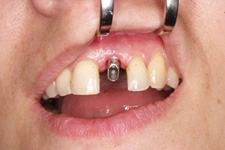

Náhrada jednoho zubu

Klasickým příkladem a indikací pro použití implantátu je ztráta jednoho zubu (v tomto případě v předním – frontálním úseku) v jinak zdravém, nepoškozeném chrupu.

Nejčastější příčinou takové ztráty je sportovní nebo dopravní úraz.

Náhrada jednoho zubu pomocí implantátu je možná také v postranním úseku chrupu. Při ztrátě většího počtu zubů ve frontálním nebo postranním úseku může být mezer uzavřena větším počtem jednotlivých implantátů.

Při ošetření pomocí jednotlivých implantátů zůstávají sousední zuby neporušené – intaktní. Při klasickém ošetření pomocí můstků musejí být tyto zuby obroušeny!